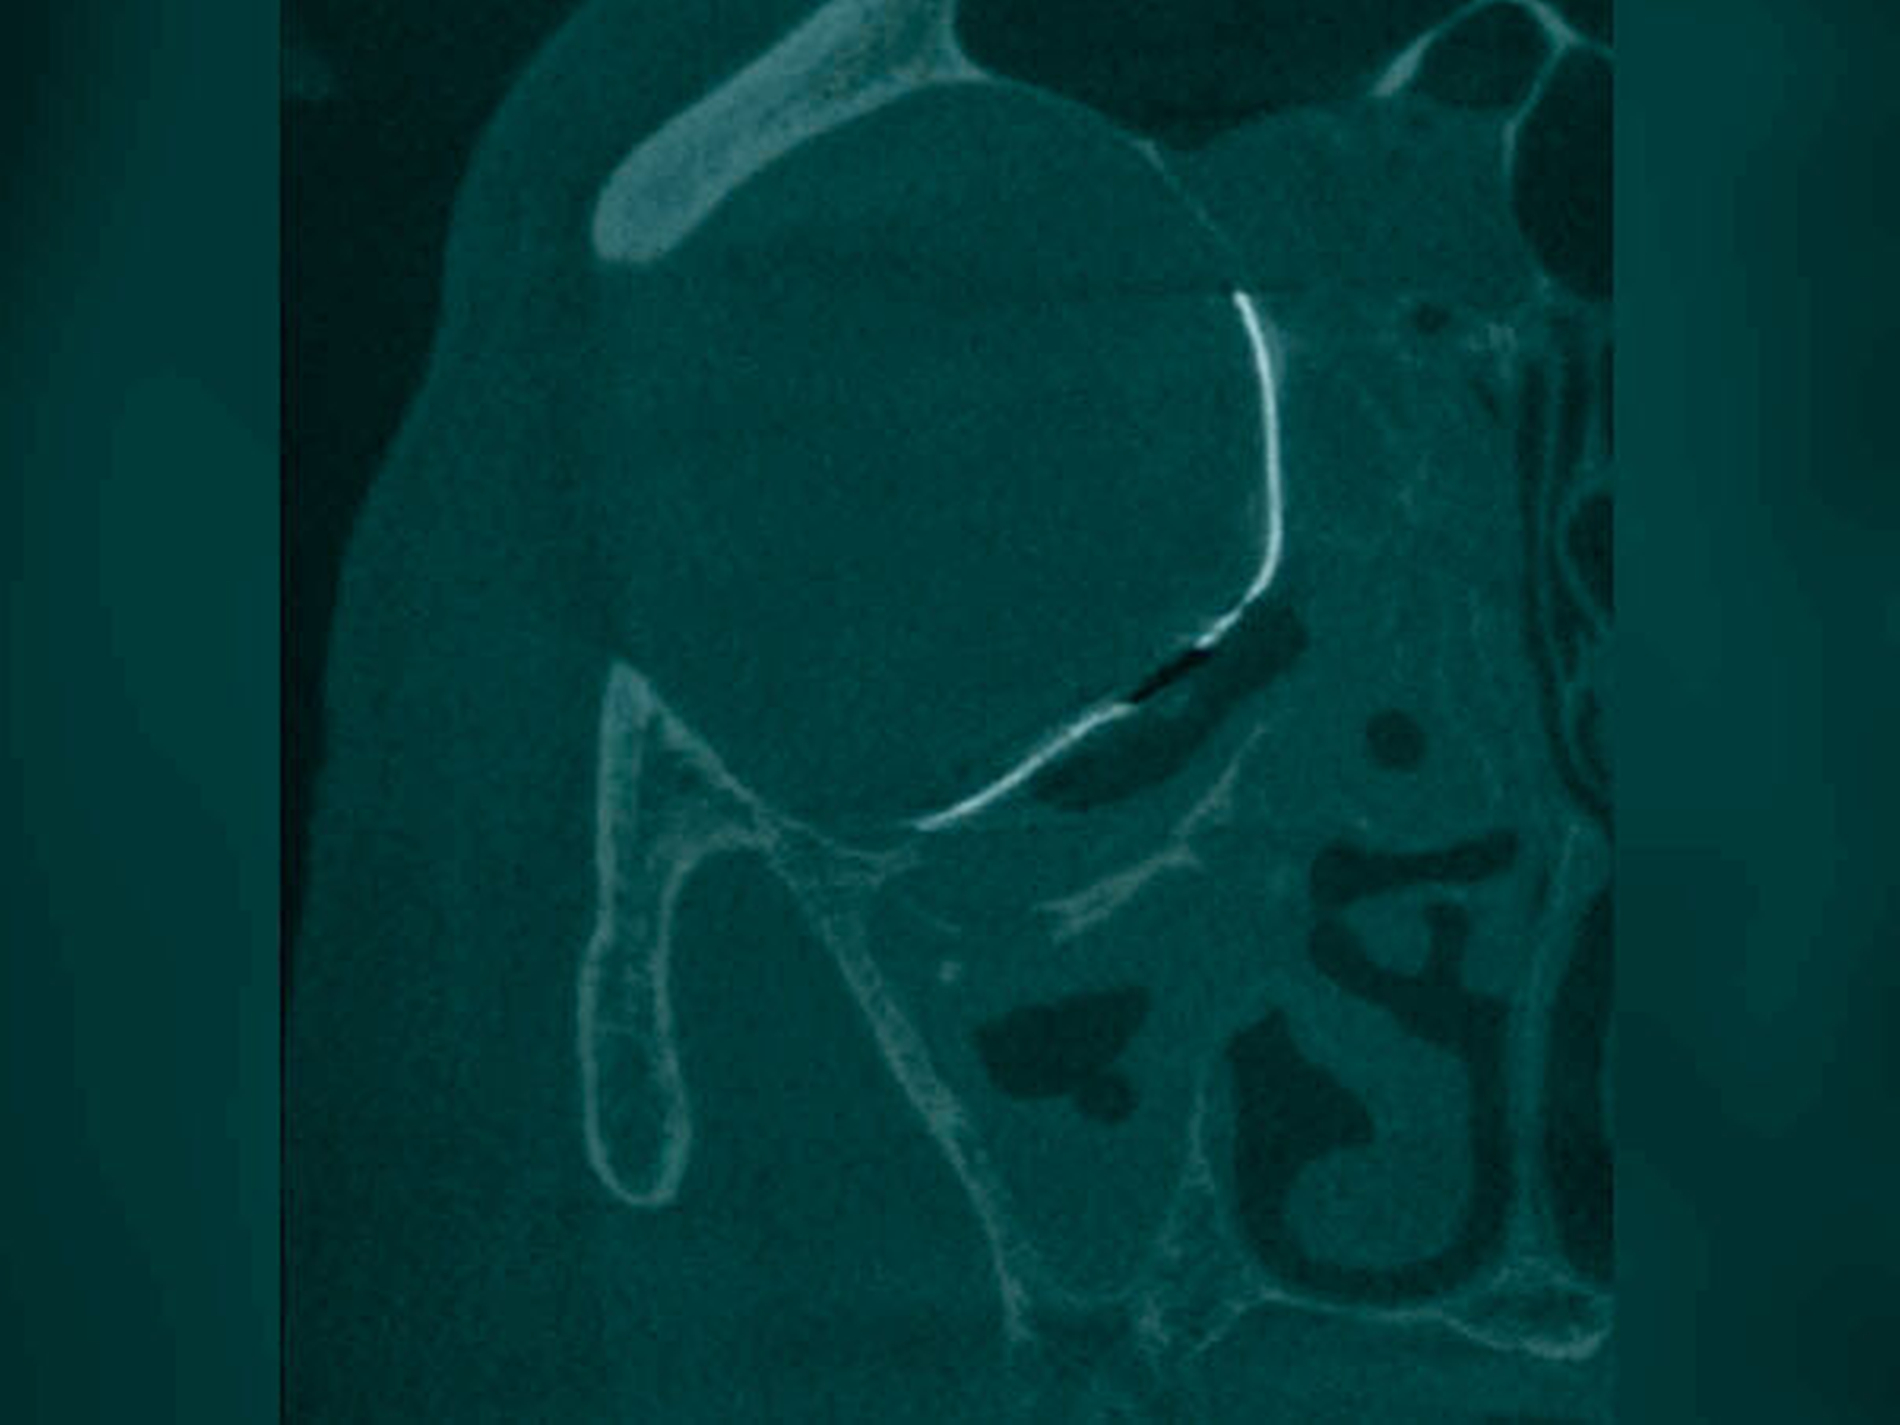

Anhand einer präoperativ durchgeführten Dünnschicht-CT kann im Anschluss gemeinsam mit dem Hersteller (KLS Martin Group, Tuttlingen) im volldigitalen Workflow (IPS CaseDesigner®) eine präzise Planung und die Anfertigung des patientenindividuellen Orbitameshs (Abbildung 3) erfolgen. Zur Rekonstruktionsplanung wird der gesunde, nicht verletzte Orbitaring digital basierend auf den oben genannten CT-Daten auf die frakturierte Seite gespiegelt. Das so generierte PSI zur Rekonstruktion des dislozierten Orbitabodens und ausgesprengter medialer Orbitaanteile wird anschließend komplikationslos unter navigationsgestützter Kontrolle über einen transkonjuktivalen Zugang in Intubationsnarkose eingebracht und unter Schonung des N. infraorbitalis mit drei Osteosyntheseschrauben verankert (Abbildung 4). Die postoperativ erfolgte, dreidimensionale Bildgebung mittels digitaler Volumentomografie (DVT) zur Lagekontrolle des PSI zeigt eine regelhafte Position mit suffizienter Anlagefläche sowohl kaudal als auch medial (Abbildungen 5 und 6).